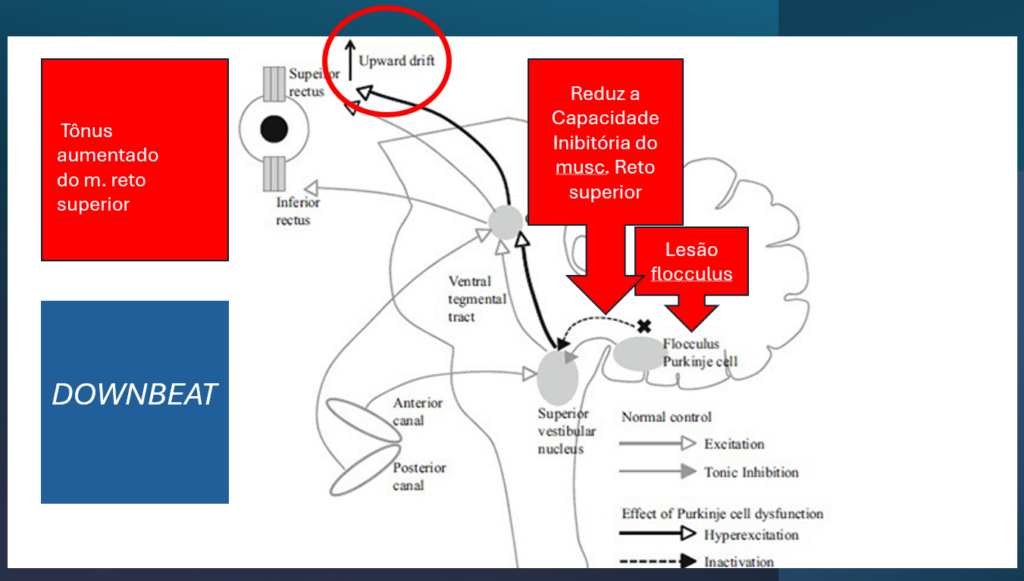

Os anticorpos contra o GAD acabam interferindo na síntese do GABA nas células de Purkinje gabaérgicas do floculo-cerebelar.

As células de Purkinje do floculo-cerebelar são especialmente sensitivas para movimentos visuais para baixo. Essa células enviam projeções inibitórias aos canais semicirculares anteriores mas não para os posteriores. Com isso, o dano flocular gera um “drive” dos olhos para cima (componente lenta do nistagmo). A formação reticular gera a componente rápida para baixo = NEVI.